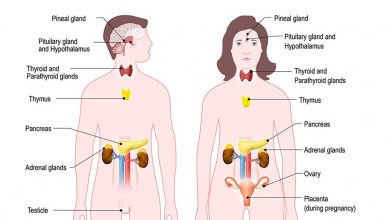

عکس داخل شکم انسان. در این همان طور که مشخص است شکم حالت بیضی شکل پیداکرده و این بیضی که کناره های شکم کشیده شده است. تعداد سلول های بدن انسان حدود ۳۷ ۲ تریلیون تخمین زده شده اند. Abdomen که در زبان عامه به غلط به آن دل نیز می گویند در آناتومی به قسمتی از تنه گفته می شود که مابین دیافراگم از بالا و سطح فوقانی لگن خاصره از پایین قرار دارد. ربات دیدنی ربات انساننمای چینی به صورت یک دختر جوان ساخته شده و جیا جیا نامگذاری شده است این ربات طوری برنامهریزی شده که میتواند صحبت کند و احساسات خود را از طریق تغییرات در چهره حالات.

شکل دوم شکم مادری را نشان می دهد که جنین دختر دارد. وحشت مادر از عکس سونوگرافی جنین داخل شکمش عکس. تصاویر جالب از داخل مغز و نخاع انسان آخرین نیوز. بدن انسان کل ساختار انسان است که سر گردن تنه سینه و شکم دو بازو و دست ها و دو ساق پا و پاها را شامل می شود.

رونمایی از جرد لتو در نقش جوکر عکس. این تصاویر عجیب و بی نظیری كه مشاهده می کنید مربوط به یك ساختمان واقع در كشور هلند است كه شبیه انسان ساخته شده و از تاریخ چهاردهم مارس 2008 برای بازدیدكنندگان فعال بوده است. فرم شکم زنان باردار دختر. هر قسمت بدن از انواع مختلف سلول تشکیل شده است.